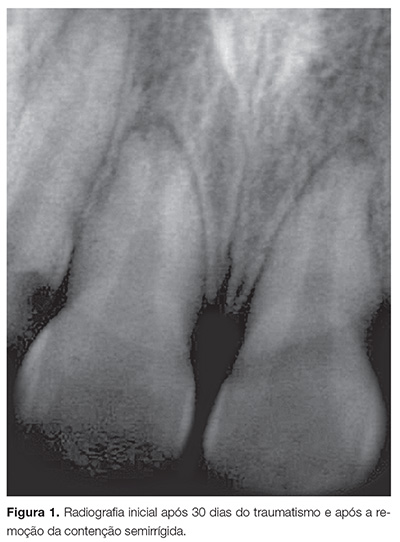

O paciente compareceu à FOP-UNICAMP um mês após o traumatismo. Durante a avaliação clínica inicial e radiográfica, observou-se que os dentes 11 e 21 apresentavam ausência de vitalidade pulpar, ausência de dor à percussão vertical/horizontal e à palpação. Foi realizada radiografia periapical (Fig. 1), podendo ser observada rizogênese completa, reabsorção radicular externa e lesão periapical nos dentes envolvidos. Diante do quadro de necrose pulpar, foi proposta realização do tratamento endodôntico por meio de uma pasta que associa hidróxido de cálcio P.A., clorexidina gel a 2% e óxido de zinco, na proporção de 2:1:2, com consistência de “massa de vidraceiro”.

A cada três meses, o paciente retornava à faculdade apenas para acompanhamento clínico e radiográfico, e era possível observar a presença da medicação/pasta preenchendo completamente o canal, excluindo a necessidade de sua renovação. Após 12 meses de tratamento, notou-se remissão da lesão periapical (Fig. 3A). Após 24 meses de proservação, verificou-se que a medicação continuava preenchendo toda extensão do canal radicular, sem necessidade de renovação, sendo possível observar a regressão da lesão periapical e paralisação da reabsorção inflamatória (Fig. 3B).